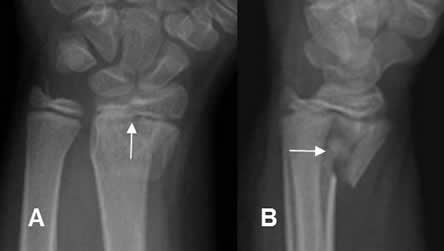

Fig 76 A. Salter tipo IV.

A: Rx AP y B: Rx lateral. Fractura impactada y con angulación anterior, en el radio distal, con compromiso de la epífisis y metáfisis.